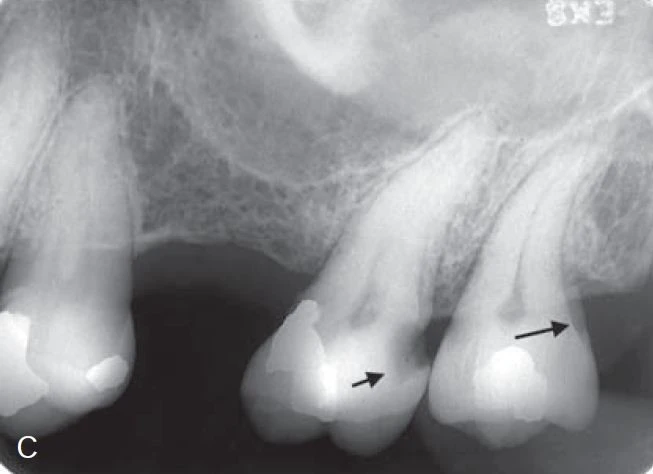

Hình 15. Tổn thương sâu răng mặt ngoài (mũi tên)

MẶT NGOÀI VÀ MẶT TRONG

Tổn thương sâu răng ở mặt ngoài và mặt trong thường xảy ra ở những hố rãnh trên men răng. Khi tổn thương nhỏ, chúng thường có hình tròn; khi lan rộng lên, chúng thường có hình elip hoặc hình bán nguyệt. Chúng có bờ rõ ràng, giới hạn rõ. Có thể khó để phân biệt giữa tổn thương mặt ngoài hay mặt trong trên X quang. Khi quan sát tổn thương mặt ngoài hoặc mặt trong, bác sĩ lâm sàng sẽ tìm thấy một vùng men không sâu răng với mật độ đồng nhất bao xung quanh một vùng thấu quang rõ ràng. Vùng hình tròn có giới hạn rõ này biểu hiện phần men răng không sâu răng song song bao xung quanh tổn thương mặt ngoài và mặt trong. Tuy nhiên, tổn thương mặt nhai thường lan rộng hơn sâu răng mặt ngoài hoặc mặt trong, và đường viền của cúng không có giới hạn rõ. Đánh giá trên lâm sàng bằng cách quan sát và thăm khám để chẩn đoán xác định tổn thương mặt ngoài hoặc mặt trong.